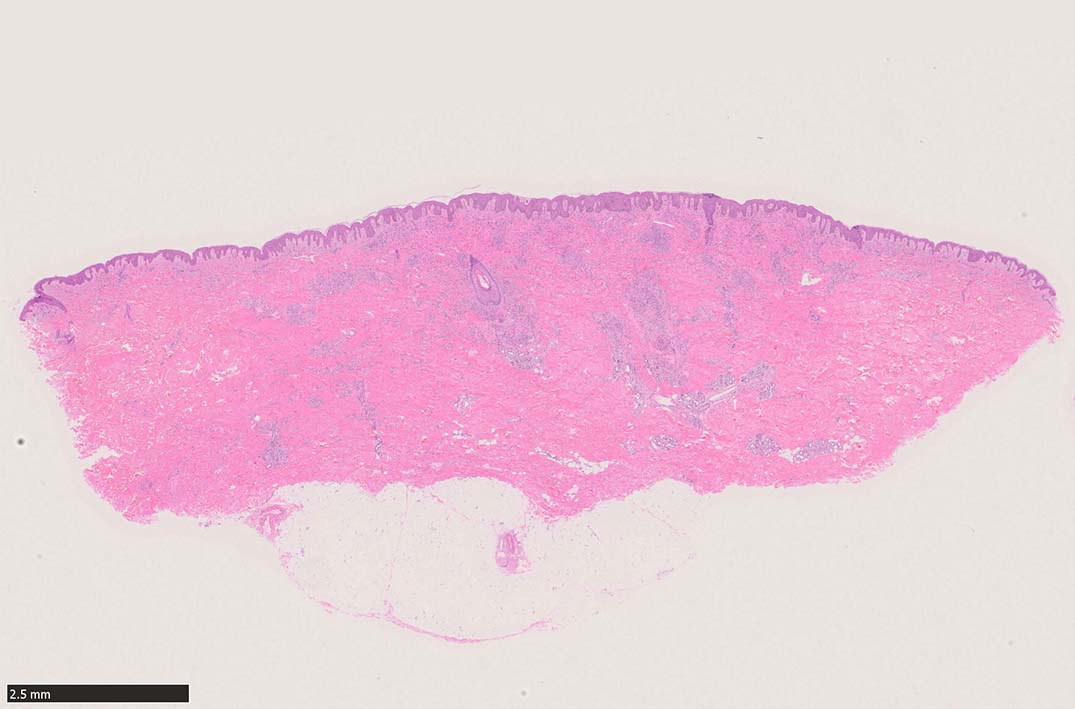

肉眼で平坦な斑状(macule)病変 --> 平板にやや盛り上がった隆起; 局面(plaque)病変 --> 更に進行し結節状(nodule)病変に進行する. (病理所見も病変の進行とともに変化している.)

初期斑状病変の病理

初期の斑状病変の組織学的所見はごく軽度の炎症反応の様相を呈し, 真皮内の正常毛細血管を囲むようにして拡張した血管内皮様細胞による管腔が認められる.

好中球などの炎症細胞浸潤はまれであるが, 形質細胞はしばしば増加している.*5

この時点ではKaposi肉腫特有の線維芽細胞様紡錘形細胞(spindle cells)は少なく, 診断はときに困難である. (HHV-8免疫染色が必須)

細血管周囲に血管内皮様の紡錘形細胞が増生, 一部に赤血球をいれた裂隙の形成がある. 細胞の異型はみられず, mitosisの増多もない. hemosiderin-laden macrophageが散在する.

病変は真皮内に現局している. 初期斑状病変に相当すると考えられる. 本例では, 特徴とされる形質細胞浸潤増加はみられない.